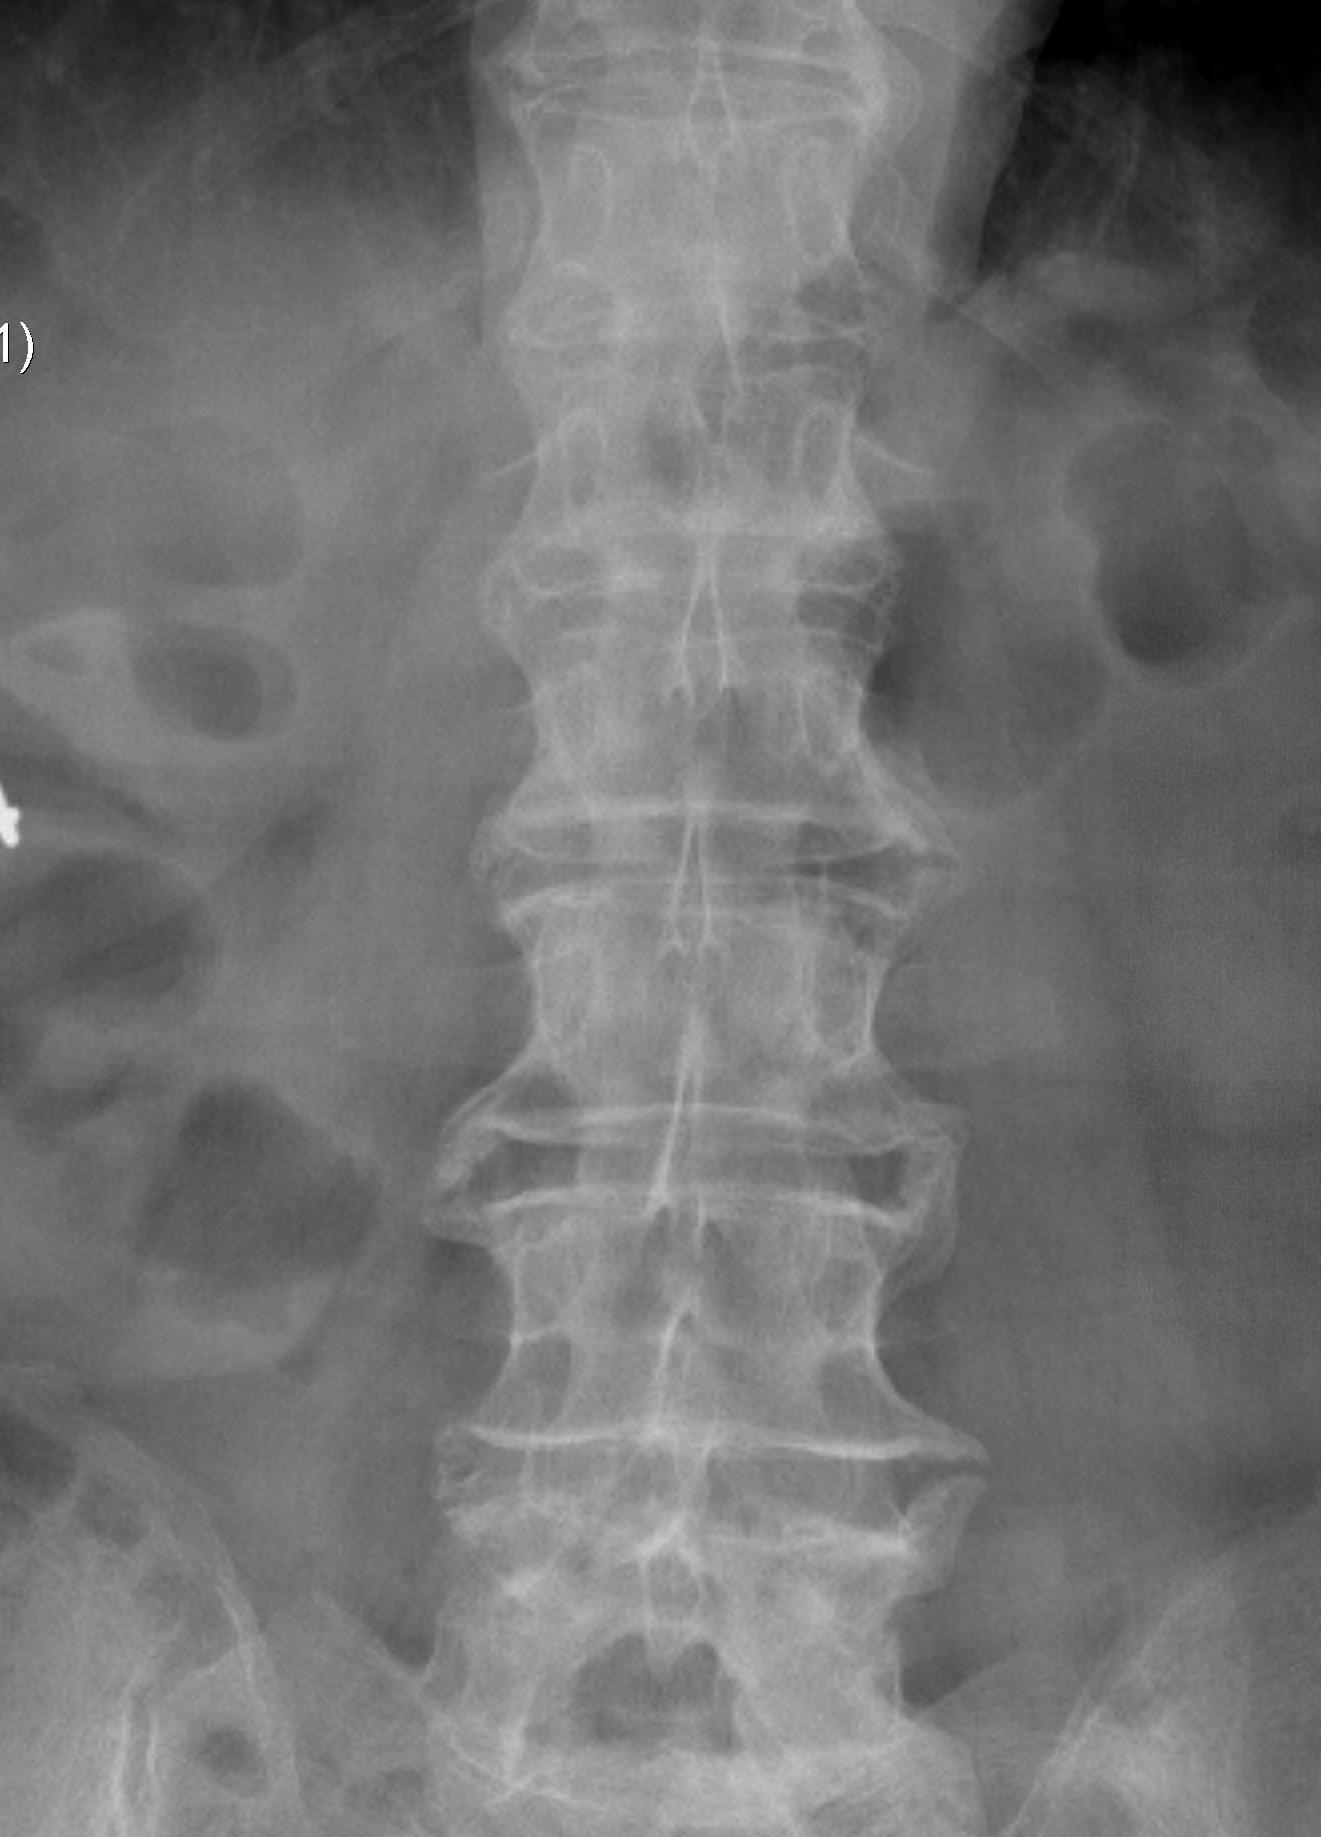

Spine

- marginal erosions / squaring of anterior body concavity

- marginal syndesmophytes

- bamboo spine

TL spine

A. Spondylodiscitis / Anderson lesion

- erosion of enthesis at anterolateral annulus at endplate

B. Romano's lesion

- lesions heal by forming new bone / early squaring

C. Marginal syndesmophyte

- with repeated episodes forms thin vertical bone due to ossification of annulus fibrosis

D. Bamboo spine

- fusion / bony disc casing